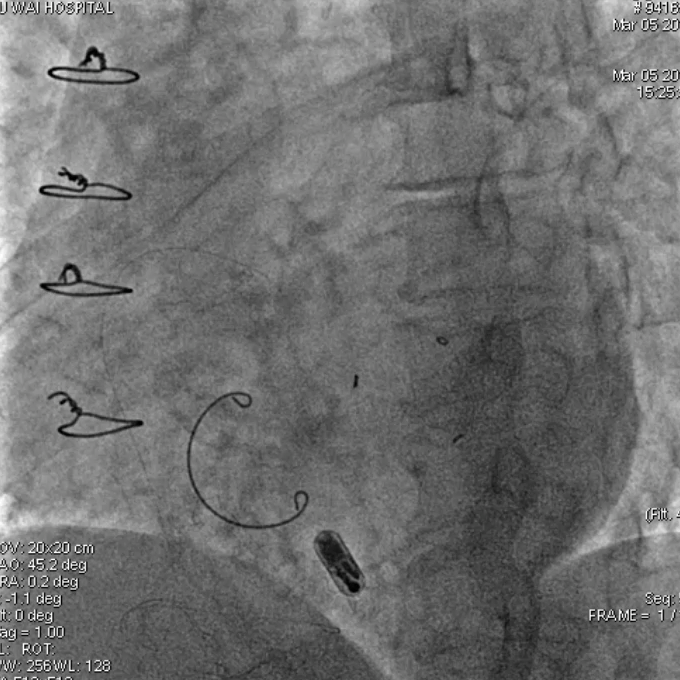

2015年,中国医学科学院阜外医院参与了Micra全球上市前临床试验,总共入组了5名患者。该临床试验为全球多中心、非随机、单臂上市前临床研究,旨在评估Micra VR无导线起搏器的安全性和有效性。该项研究的结果发表在2015年新英格兰医学杂志上,研究结果表明,Micra VR无导线起搏器手术成功率为99.2%,其不良事件发生率相对于传统起搏器降低了48%。

近期,中国医学科学院阜外医院将10年前入组的5名无导线患者在十年内的随访数据加以整理汇总,汇编了国内首批应用无导线疗法的长期的、真实世界临床结果。

5名患者中, 2名患者因恶性肿瘤及肺部感染分别于2019年和2022年离世。3名患者随访已达到10年,相关数据整理如下